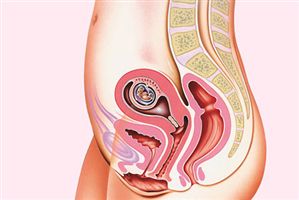

Фото: 3 тиждень вагітності

3 тижні вагітності. фото плода